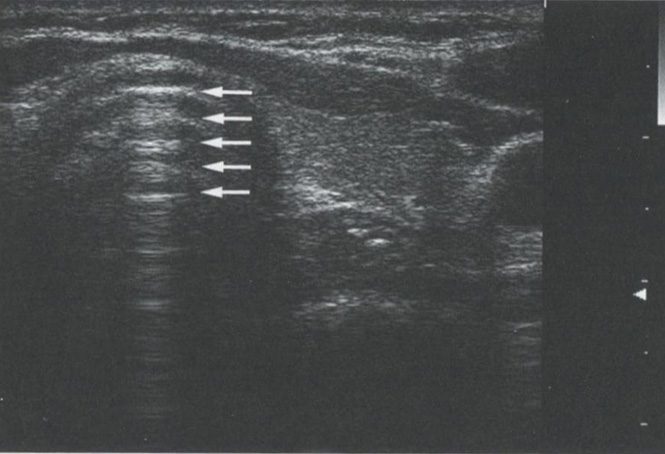

Когда звуковые волны попадают на область с сильно выраженной разницей акустического импеданса, например, на границу ткань-воздух или на кальцинат, подавляющее большинство звуковых волн отражается, обеспечивая очень яркий сигнал, исходящий от поверхности объекта, и отсутствие изображения за его пределами. Рис. 2.9 демонстрирует акустическую тень за кальцинированным узлом. На рис. 2.10 изображен грубый кальцинат в паренхиме щитовидной железы (ЩЖ) с акустической тенью позади кальцината. Рис. 2.11 показывает типичную картину

Рис. 2.9. Акустическая тень. Когда звуковые волны попадают на область с выраженной разницей акустического импеданса, например, на границу ткань-воздух или на кальцинат, подавляющее большинство звуковых волн отражается с возникновением тени кзади от исследуемой структуры. Этот кальцинированный узел наблюдался у пациента с семейной формой папиллярного рака трахеи при УЗИ. Поскольку звук через воздух не проводится, изображение задних структур трахеи отсутствует.